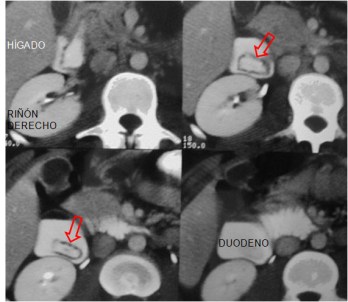

SIGNO DEL HALO

Signo de divertículo duodenal intraluminal en el tránsito baritado y en la TC. El signo recibe el nombre por la imagen lineal radiolucente que queda entre el contraste baritado que rellena el divertículo y el de la luz duodenal, y que corresponde a la pared del divertículo.

La secuencia de cortes en el TC abdominal con contraste oral e intravenoso en el mismo paciente, muestra el signo en el divertículo intraluminal duodenal.

El divertículo duodenal es una rara anomalía del desarrollo que, a diferencia de la atresia duodenal, no provoca obstrucción completa de la luz ya que la fijación del divertículo a la pared duodenal afecta a menos de la mitad de la luz o, si es mayor, éste presenta una fenestración que permite el paso del contenido alimenticio.

Las imágenes de este caso están tomadas del artículo de Sanchis-Querol, E y cols. Divertículo duodenal intraluminal como causa de pancreatitis recidivante. Diagnóstico mediante TC. Radiología 2000; 42: 566-568. Han sido incluidas en este trabajo con permiso de la SERAM.